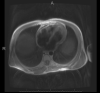

Constrictive pericarditis is a rare cause of right-sided heart failure secondary to a stiff, non-compliant pericardium. Clinical presentation can vary considerably and requires a high suspicion for diagnosis. A 31-year-old male presented to the emergency department with complaints of abdominal distension. An abdominal ultrasound revealed large volume ascites; thus, it was initially suspected he had underlying cirrhosis. However, an echocardiogram revealed a diagnosis of constrictive pericarditis. It's important for clinicians to consider constrictive pericarditis in a patient presenting with unexplained right-sided heart failure.

Keywords: Cardiac MRI; Echocardiography; Pericardial Diseases.